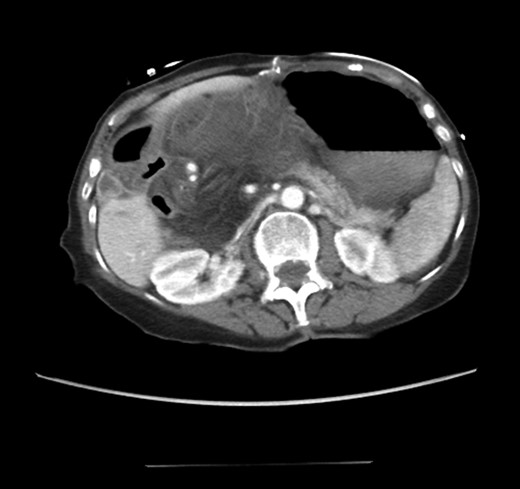

CT scan from four years prior to presentation showing evidence of foramen of Winslow hernia. Arrow head on stomach. Arrow on bowel.

Diagnosing an internal hernia is frequently accomplished using physical exam and CT imaging. Abdominal X-ray does have some nonspecific findings suggestive of internal hernia but is usually inadequate for diagnosis. Diagnosis of a foramen of Winslow hernia, however, is only accomplished in 10% of patients preoperatively [3]. As previously mentioned this diagnosis is rare and often presents with vague obstructive type symptoms. This likely contributes to the low occurrence of accurate preoperative diagnosis. However, several radiographic findings were seen in this patient that suggested a foramen of Winslow hernia preoperatively. First, there is visible swirling of the mesentery on the CT scan that is indicative of internal hernia (Fig. 1). Second, there are loops of small bowel that can be visualized between the IVC and the edge of the liver in a supra renal position along the lesser curvature of the stomach (Figs 1 and 2). When compared to a CT of the abdomen and pelvis obtained 4 years prior to presentation, there is actually evidence that this patient had a non-obstructing foramen of Winslow hernia at that time as demonstrated by bowel being visualized in the lesser sack (Fig. 5). These findings, especially small bowel along the lesser curvature of the stomach, are inconsistent with normal anatomy and strongly indicative a foramen of Winslow hernia.